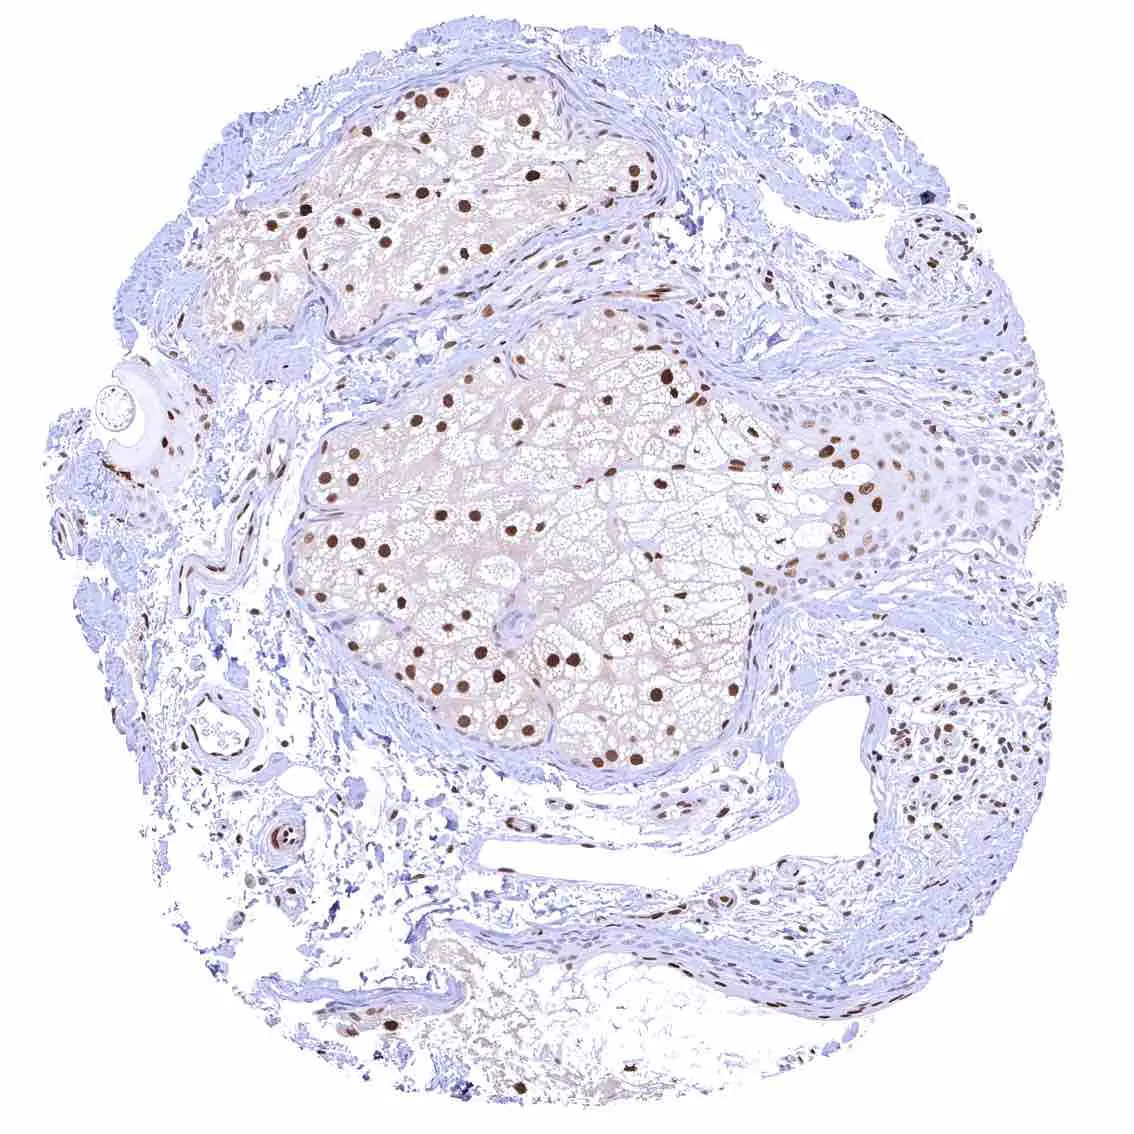

Breast – Moderate to strong nuclear p27 positivity of a large fraction of glandular epithelial cells.